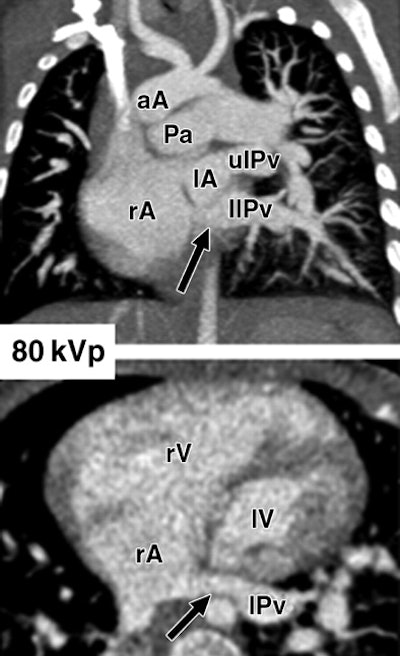

| Images show three different examples of congenital vascular abnormalities of chest evaluated with 64-slice CT with use of automatic tube current modulation. Oblique coronal maximum intensity projection images (upper row, above) and transverse section images (lower row, above) of patients scanned at 80 kVp and 100 kVp. Image set A (above) shows stenotic pulmonary artery (black arrowheads) in 6-month-old girl. Note difference in vessel caliber between right and left pulmonary arteries (white arrowhead). Image set B (below) shows left lower pulmonary vein (llPv) draining (black arrows) in right (rA) instead of left (lA) atrium in 2-year-old boy. ulPv = upper left pulmonary vein, rV = right ventricle, and lV = left ventricle. Image set C (100 mAs, bottom) shows tetralogy of Fallot with large septal defect (white arrows), overriding ascending aorta (aA), and stenotic pulmonary artery (Pa) in 6-month-old boy. |